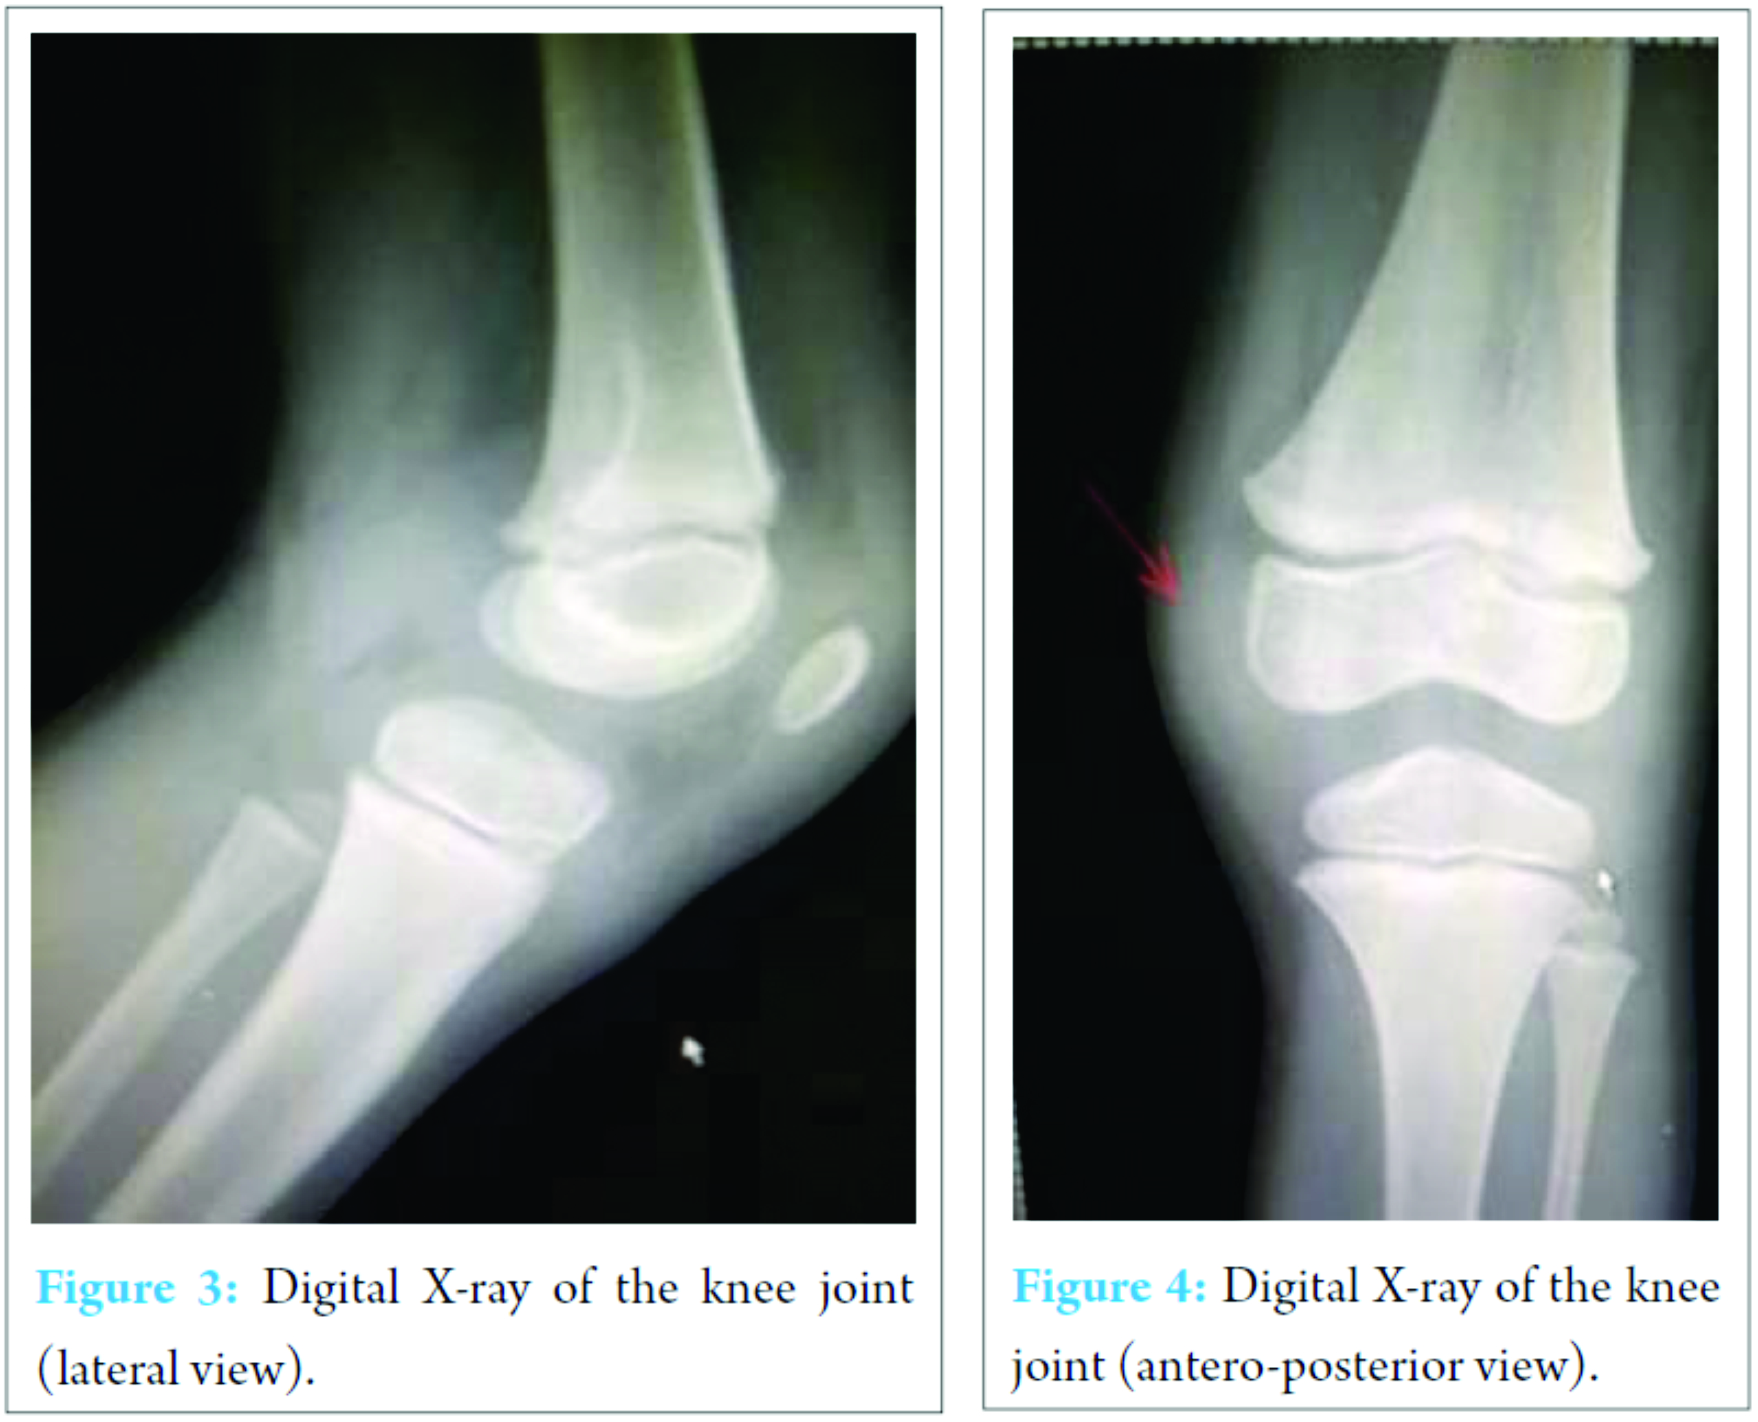

X-ray of the knee joint was unremarkable (Fig. 3, 4). Ultrasonography (USG) revealed a hypoechoic well-defined cystic lesion with clear contents is visualized on the antero-medial aspect of the left knee over the semitendinosus tendon. The lesion measures 25 mm × 10 mm. The lesion is causing splaying of the gracilis and sartorius muscles near knee; the lesion extends lower down and posteriorly and appears to fuse close to pes anserine insertion near the pulsation of the medial geniculate artery (Fig. 5, 6). Doppler USG showed no evidence of vascular involvement.

USG and magnetic resonance imaging (MRI) can differentiate a ganglion cyst from other soft tissue lesions and provide excellent information about the location and dimensions of the lesion along with its margins especially intratendinous cysts [1, 3, 16].

Intratendinous ganglion cyst is a relatively uncommon lesion. Incidence of the upper limb is more common than lower limbs. All cysts around the joints and tendons should undergo USG evaluation both preoperatively as well as postoperatively. We have presented the first case report of an intratendinous ganglion cyst of the semitendinosus tendon with findings using USG.